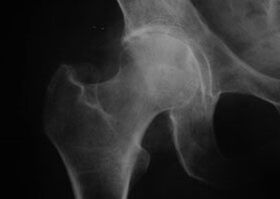

artropatía de cadera, artrosis de cadera

En esta enfermedad se pueden observar manifestaciones clínicas típicas de artropatía.

El primer síntoma de la artritis de cadera es la molestia en la articulación de la cadera después de la actividad física.

La artritis progresiva de la cadera conlleva un aumento del dolor, la rigidez y la movilidad limitada.

Los pacientes con enfermedad grave de la cadera deben proteger la extremidad afectada, evitar pisarla y elegir una posición que minimice el dolor en reposo.